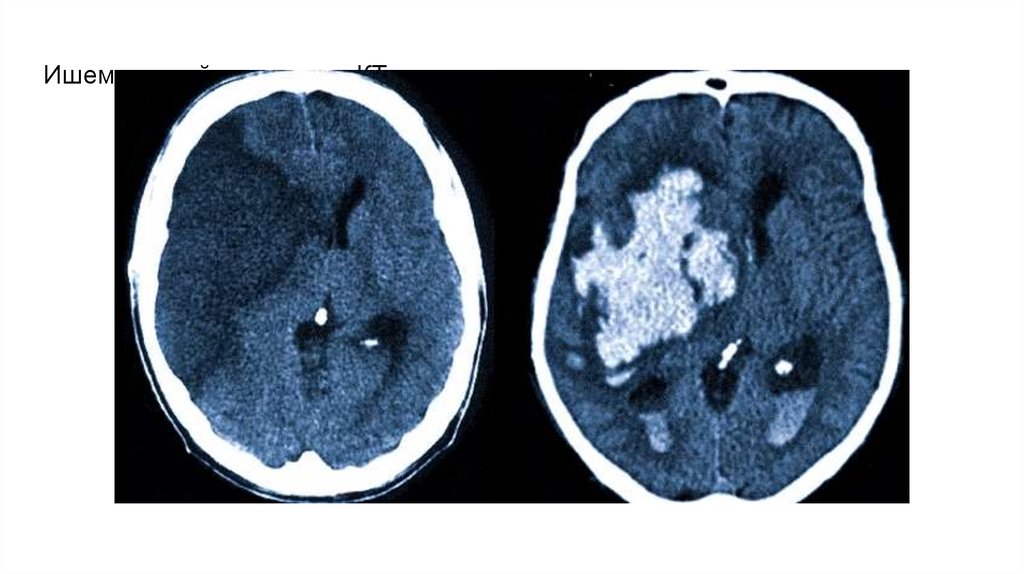

Ишемический инсульт на КТ